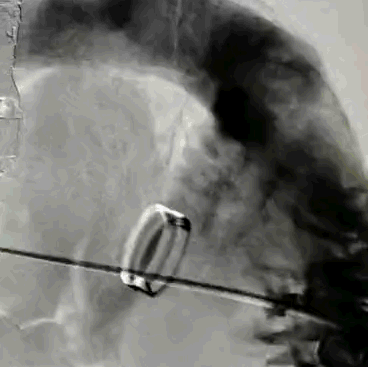

瓣膜植入前右心室造影